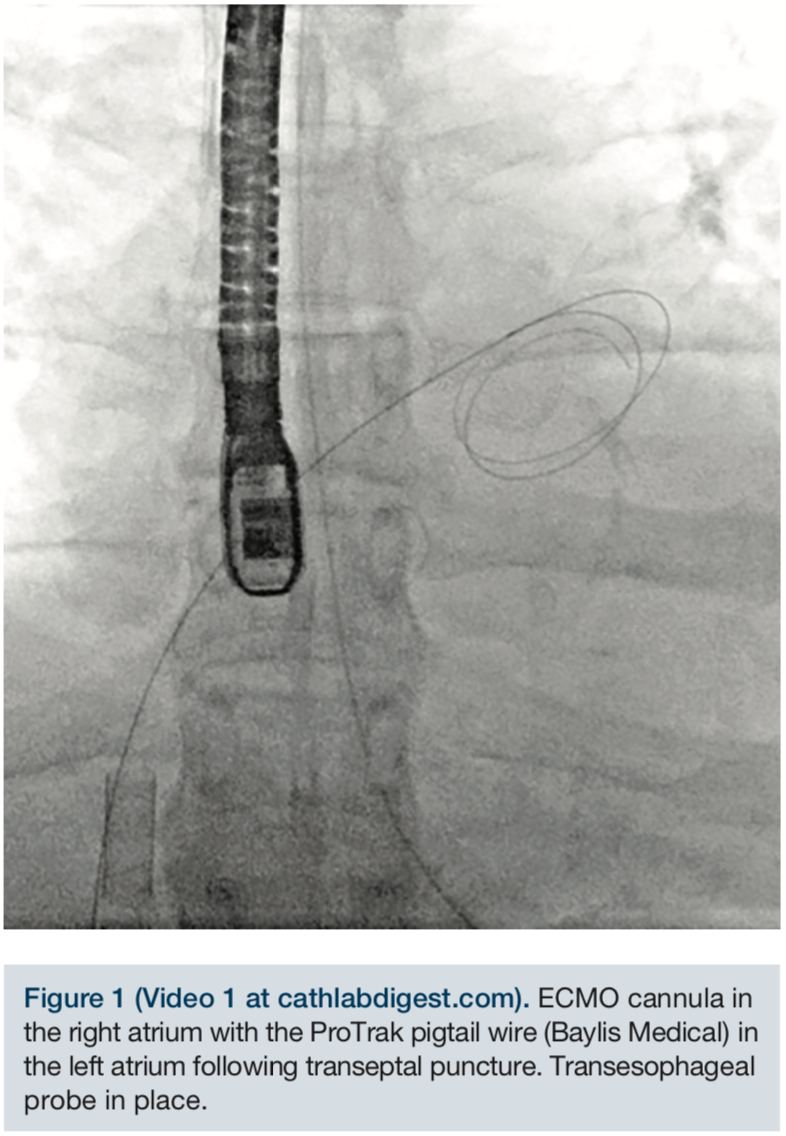

Through a 6 French femoral venous sheath, an 0.032-inch Amplatz Extra Stiff guidewire (Cook Medical) was placed into the superior vena cava and the sheath removed. An 8 French SL1 sheath (St. Jude Medical) was advanced over the guidewire into the superior vena cava. Care was taken not to interfere with the ECMO cannula. Using standard technique under transesophageal guidance, the 71cm BRK transeptal needle (St. Jude Medical) was used to obtain a high and posterior puncture. The SL sheath was advanced into the left atrium. A ProTrack pigtail wire (Baylis Medical) was advanced into the left atrium. The 24 French steerable guide catheter was successfully negotiated across the intra-atrial septum and advanced into the left atrium using appropriate maneuvers.